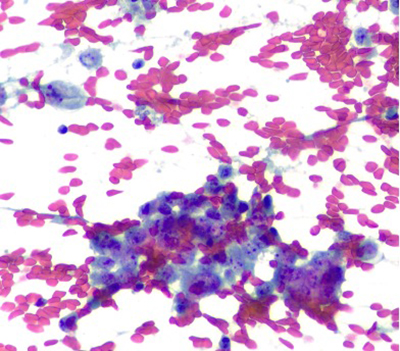

The aspirate was hypercellular and composed of small round cells, distributed in clusters of loosely cohesive clusters and as isolated cells. Moderate pleomorphism, hyperchromasia and variably prominent nucleoli were noted. On cell block preparation, the cytoplasm of these cells had a cleared appearance. Geographic necrosis was noted, with viable cells present in perivascular areas. Focally, there was an extracellular myxoid matrix.

Papanicolaou stain (400X)

Giemsa stain (400X)